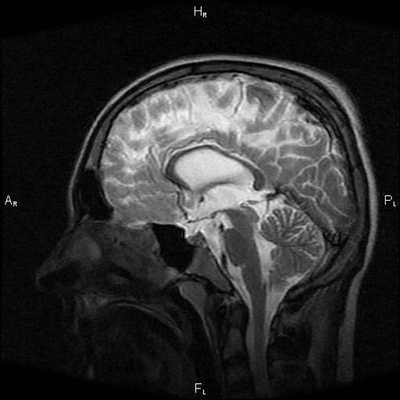

Пациентка Ш. 83 лет

Проблема: жалобы на снижение памяти, повышенную утомляемость. Пациентка была направлена на МРТ головного мозга с целью исключения различных патологий.

При МРТ головного мозга установлено: МРТ признаки хронической недостаточности мозгового кровообращения; выраженная открытая внутренняя гидроцефалия, свидетельствующая о признаках атрофических изменений в головном мозге.